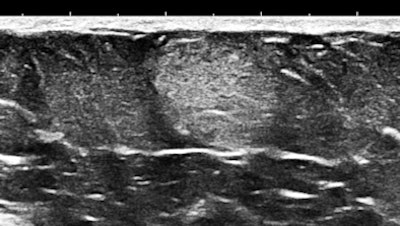

Here are three representative (HD) anterior abdominal wall images at 15 MHz:

Mast cells and mediator-release disorders

These echogenic "nodules" are tumorlike collections and cellular infiltrates of mast cells. The precise diagnosis is systemic mast cell disease. Symptoms are due to mediator release. At one pole is typical carcinoid syndrome involving serotonin and kallekrein, and at the other extreme is anaphylaxis with predominant histaminelike substances. Because of the large number of nodules, there is a significant neuroendocrine burden, similar to the multiple metastases of a malignant carcinoid tumor filling the liver.

Soft, well-demarcated reflective nodules in subcutaneous fat are an Aunt Minnie of a sign. They are not palpable, and I suspect they can only be found by high-frequency ultrasound, which is perfect for outpatient screening applications. There may be a completely unexpected, relatively high prevalence of this finding, and it seems that multiple nodules may predispose several allergic disorders, including conditions such as irritable bowel syndrome (IBS), fibromyalgia, and possibly even exercise-induced asthma or postexertional hypotension and reactive tachycardia.